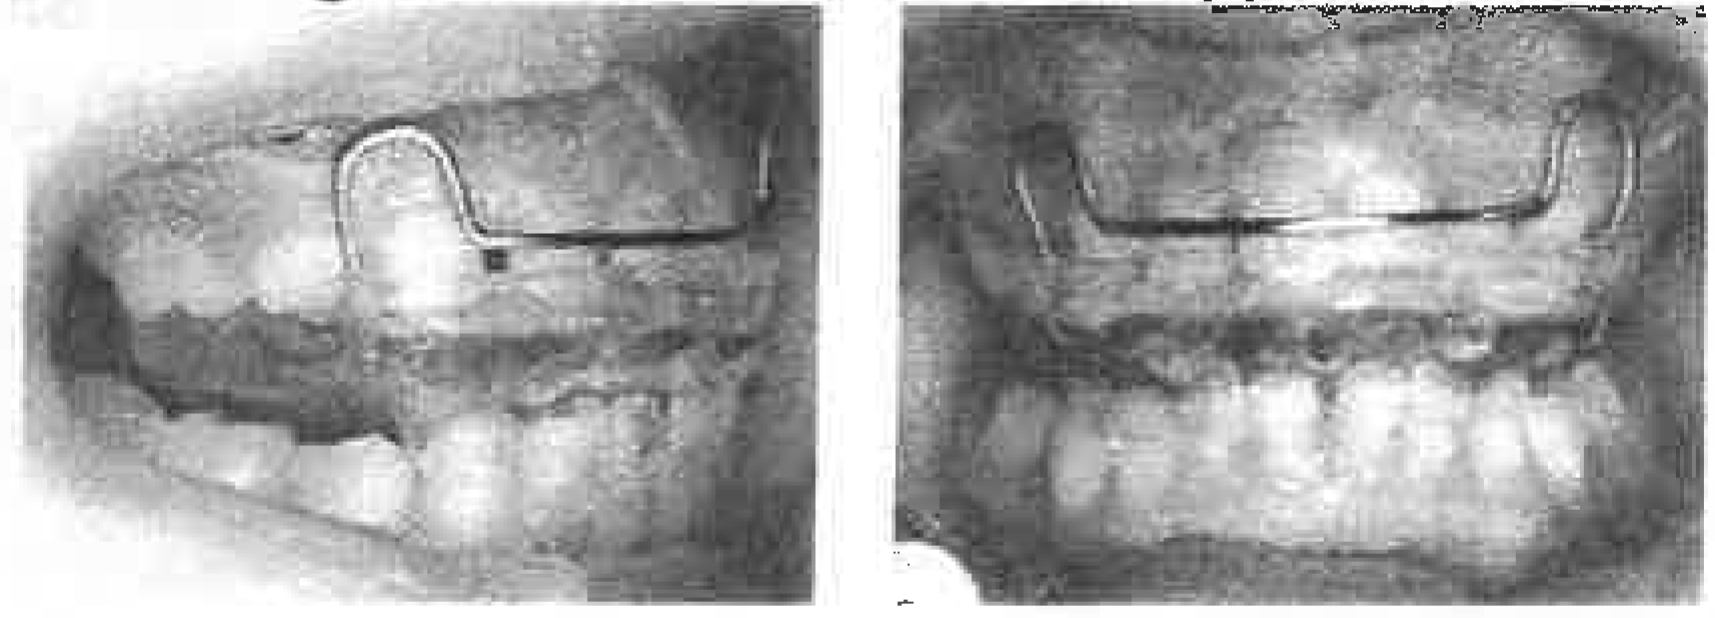

Figure 7. Case 2 - lntraoral photographs.

In the frontal view of the face, lip sucking and lip biting were noted, along with facial symmetry. In profile, the upper lip was protrusive, while the chin was retruded with mentalis strain upon lip closure. lntraorally, the patient had a severe overjet and a deep overbite with the lower incisors biting into the palate. Occlusal relationship was of mesial step type with 8.5mm of overjet and 5.0mm of overbite. The midlines were on. The cephalogram showed labial tipping of the upper deciduous central incisor, lingual tipping of the lower deciduous central incisor and mandibular retrusion (Figure 7).

TREATMENT RESULTS

Molar relationship is at present Angle Class I with 6.0mm of overjet and 4.5mm of overbite. There is minor spacing in the upper anterior area and mild crowding in the lower anterior area. Comparison of cephalograms at the start and before the end of F.A. wear in the primary dentition showed changes in SNS from 70.2° to 70.9°, ANS from 6.0° to 4.6°, Mand. pl. from 76.5° (to LA) to 90.1° (to L1) and UA-SN from 91.6° to 91.5°.

Successful breaking of the lip-sucking and lip-biting habits and stimulation of forward mandibular growth led to normalization of jaw and incisor relationships and simultaneous improvement of lip protrusion and facial profile. Both the patient and the parents were satisfied with the results. F.A. with an expansion screw was effective in expanding the upper and lower arches and thereby eliminating the mild crowding in the mixed dentition (Figure 9 and Figure 10) (Table 3).